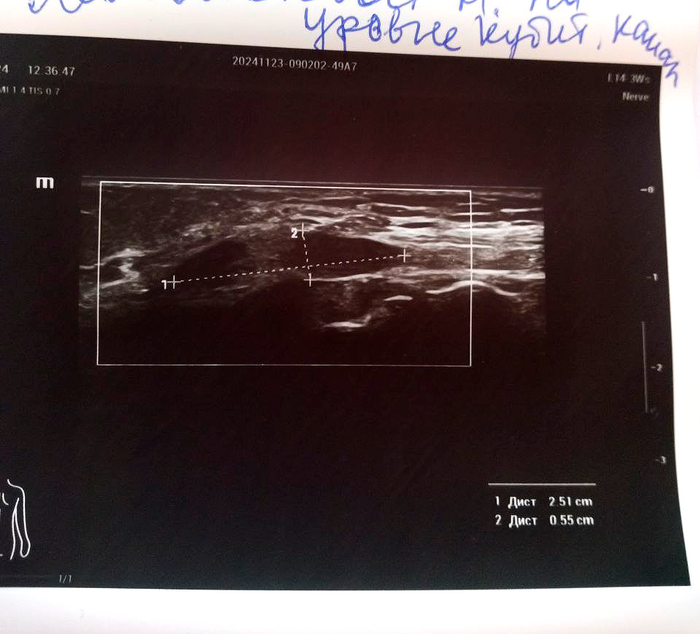

Врач-нейрохирург, специализирующийся на подобных случаях, пересмотрел полученные изыскания и проверил работоспособность конечности. Вердикт был суров - ситуация тяжёлая, но поправимая. Вся рука функционирует отлично, даже с учётом двух месяцев в повязке. Сустав в плече работает плохо, потому что разрабатывать его не даёт боль, но лучше починить старое, чем потом привинчивать новое. Пилюльки для снятия нейропатической боли прописаны правильные, но дозировку нужно больше раза в два. Плюс добавить антидепрессанты, которые так же работают со снятием боли, пусть даже будут жёсткие побочные эффекты. И быстренько разрабатывать руку, как только боль немного спадёт. Разработаю руку - победю. Пожалею себя - будут плохие последствия.

Диагноз невропатолога Комплексный регионарный болевой синдром подтверждён. Руку не отрезаем, нервы не трогаем, посттравматическая нейропатия лучевого нерва под вопросом.